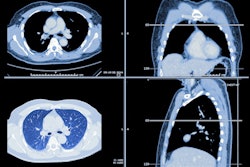

Artificial intelligence (AI) software developers Aidoc and Imbio have formed a partnership to develop an AI package for the detection and quantification of pulmonary embolism (PE).

The end-to-end platform will prioritize cases of suspected PE and automatically calculate right ventricle/left ventricle (RV/LV) ratio, bringing together Aidoc's computer-assisted triage offering for PE with Imbio's quantitative imaging software, according to the vendors.